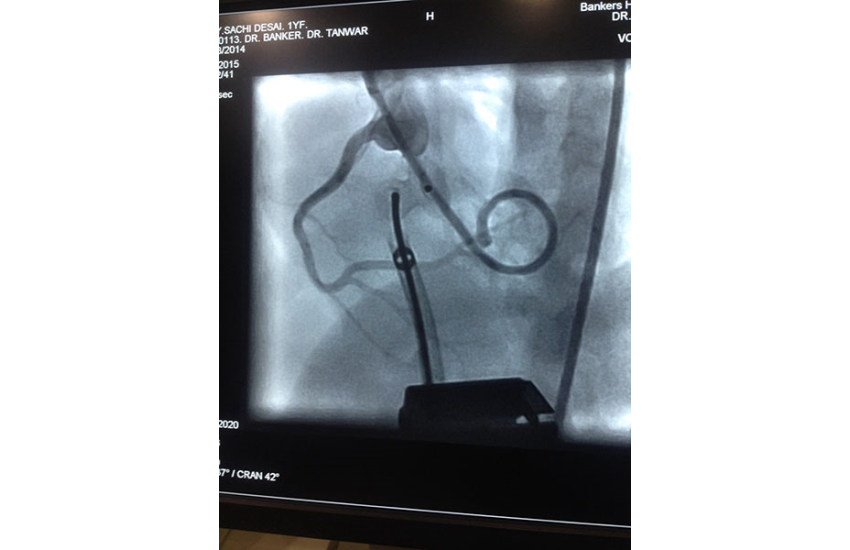

1 year girl with 7 kg weight successfully undergone Ventricular Septal Defect device closure.